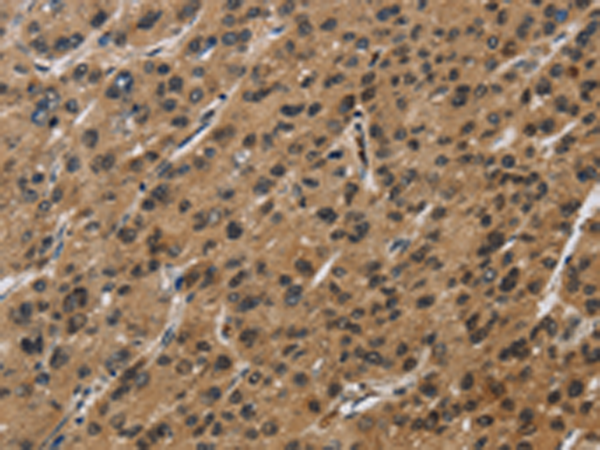

分类: 科研抗体货号: P11831别名: AME; AME1; HSD2; HSD11K; SDR9C3应用: WB,IHC反应种属: Human